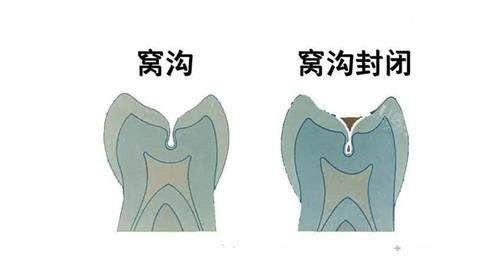

除了常见的儿童牙齿治疗项目外,郑州快乐蜗牛口腔还提供齐全的口腔服务。包括儿童牙齿预防保健,如涂氟、窝沟封闭等,帮助孩子预防龋齿的发生;早期牙齿矫正,针对一些有牙齿不齐倾向的孩子,进行早期干预和矫正,避免问题进一步恶化;以及口腔健康教育,通过生动有趣的方式向孩子和家长传授正确的口腔护理知识,培养孩子良好的口腔卫生习惯。